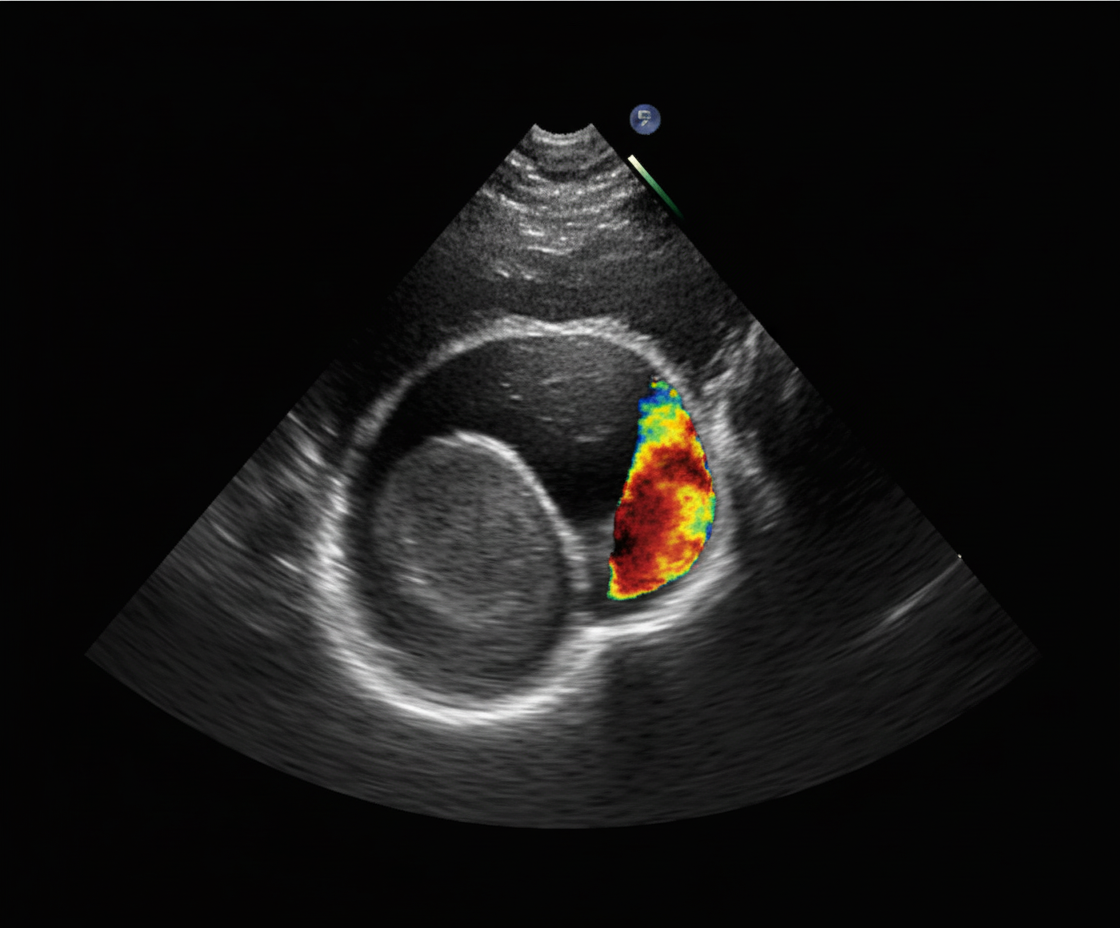

The echocardiogram of a patient presenting with exertional dyspnea, bilateral pedal edema, and elevated jugular venous pressure is shown. What is the most likely diagnosis?

Explanation: ***Tricuspid regurgitation*** - **Exertional dyspnea**, **bilateral pedal edema**, and **elevated jugular venous pressure** indicate **right heart failure**, characteristic of tricuspid regurgitation. - Echocardiogram shows **right ventricular dilatation** and **tricuspid valve insufficiency** with a **regurgitant jet** into the right atrium. *Aortic regurgitation* - Typically presents with **wide pulse pressure**, **diastolic murmur**, and **left ventricular volume overload** on echocardiogram. - Clinical features include **water hammer pulse** and **head bobbing**, not right-sided heart failure signs. *Mitral regurgitation* - Causes **left atrial enlargement** and **left ventricular dilatation** with **pulmonary edema** rather than peripheral edema. - Presents with **apical systolic murmur** radiating to the axilla and **left heart failure** symptoms. *Cor-triatriatum* - A rare **congenital anomaly** with **fibromuscular membrane** dividing the left or right atrium. - Usually presents in **childhood** with **pulmonary congestion** and requires surgical correction, not typical adult presentation.